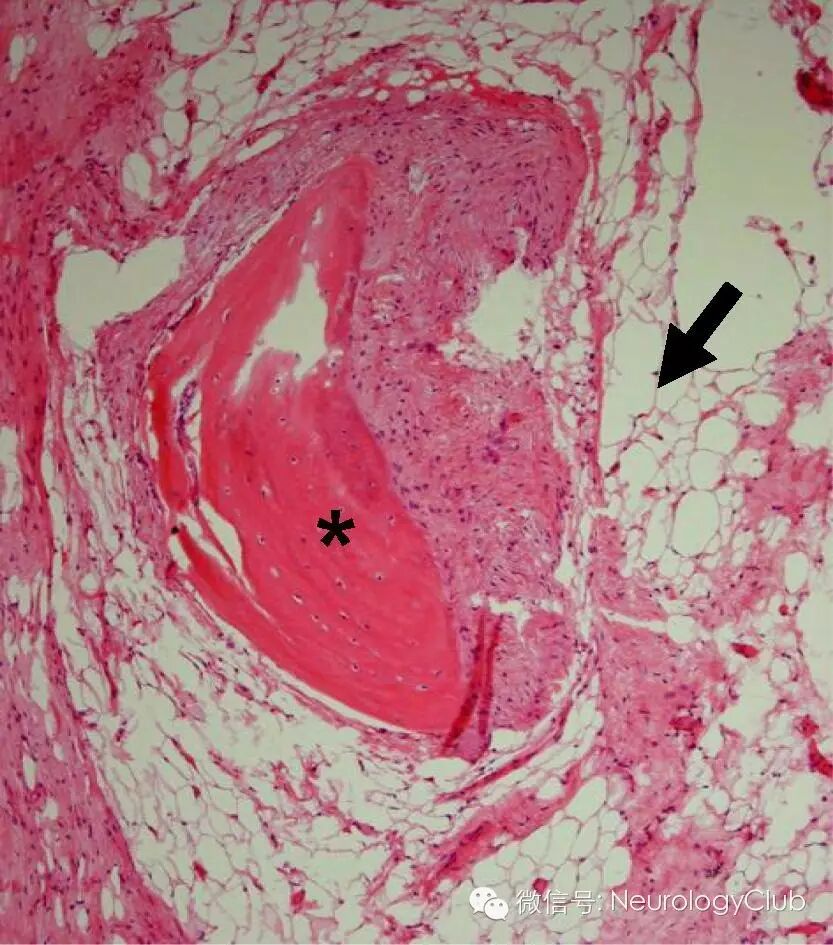

(*所示为成熟骨骼;→所示为脂肪组织 HE ×100)

畸胎瘤

性腺外畸胎瘤多起源于异位的全能原始生殖细胞,这些细胞在早期胚胎发生时错位或经历了异常的迁移。畸胎瘤内为多种混合组织成分,多达90%的儿童畸胎瘤内包含来自三个胚层的成分(外胚层的,中胚层和内胚层)。这与表皮样或者皮样囊肿不同,后两者均为外胚层来源。

尽管皮样囊肿中存在皮脂腺,可产生液体油性皮脂,在CT上表现为脂肪密度,MR上为短T1信号,脂肪抑制序列上信号衰减,但没有固体脂肪组织,因为脂肪细胞是中胚层起源。类似的,皮样囊肿中可有半成齿,但没有软骨或骨。需要注意的是,影像学上未见脂肪或骨骼并不能除外畸胎瘤。

本例患者CT上可见脂肪和骨组织,是诊断的关键。混合性囊性和实性强化肿块中同时存在上述组织,高度提示畸胎瘤的诊断,而在皮样囊肿中,强化罕见。MR进一步证实了脂肪组织的存在。病理学明确畸胎瘤的诊断。